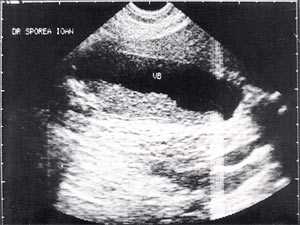

Кроме типичного вида, "желчный сладж" может иметь особый вид, похожий на круглое полипоидное объемное образование с острыми краями или неравномерным контуром ("опухолеподобный желчный сладж" или "сладжевые шарики" [12, 13]). При изменении положения больного видны перекатывающиеся или разрушающиеся шарики сладжа, затем снова формирующие исходное объемное образование (рис. 2-8).

Рис. 2. Желчный пузырь, наполовину заполненный сладжем.

Рис. 5. Желчный пузырь, заполненный сладжем, у больного циррозом.

Рис. 6. Желчный пузырь и "желчный сладж".